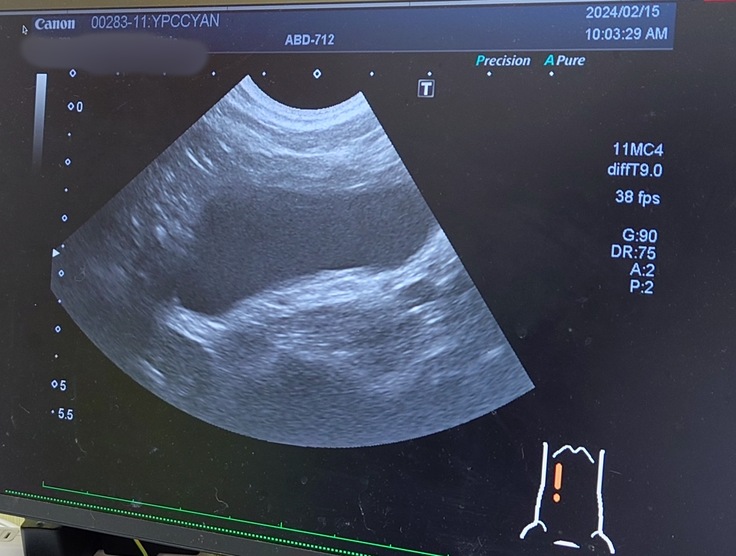

🐈「なるほど。今日はエコー検査と血液検査と尿検査と触診ですか。さぁ、やりましょうか。」

🐈変わらず、腎臓と腎盂は肥大したままのヨッちゃん🐈

🐈尿管も拡張したままだった。前回と変わりなく現状維持といったところ。🐈

今回も通院を頑張ってくれたヨッちゃん。定期的な尿路感染を起こしていないかの検査とサプリと薬の処方はかかりつけの動物病院でやってもらって、尿路感染を起こした場合やその可能性がある場合、腎臓腎盂の肥大や尿管拡張に変化が診られた場合は市外の専門の動物病院で詳しく診てもらうという予定になりました。消化器サポート系の療養食と尿の健康を維持するサプリとうんちを柔らかくするお薬を飲みながら、尿路感染を起こさないように、現状維持を保てるようにヨッちゃんにも頑張ってもらいながら1日1日を過ごしていきたいと思います😊